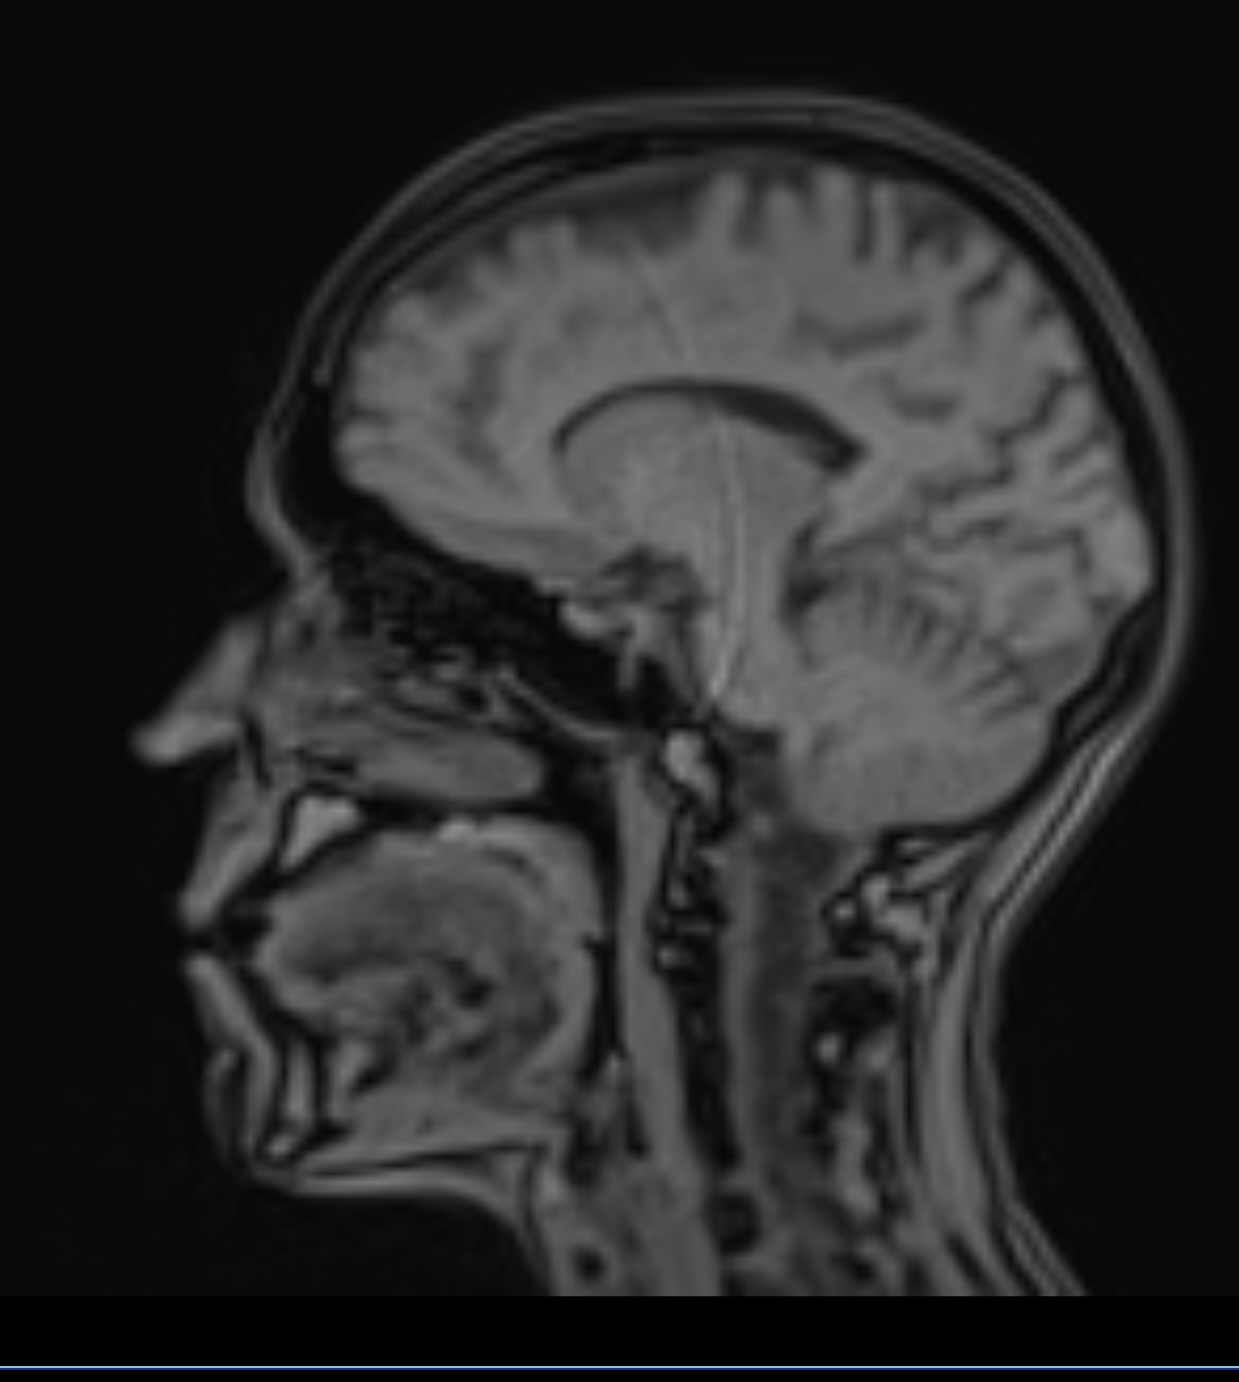

It looks to me like what is called an ‘artifact’ or glitch in the recording process. There is NO WAY a catheter, or probe, etc. would have such a circular looking path through all those layers of cortex, midbrain, corpus callosum, etc. Also bear in mind that MRIs are rendered one slice at a time, and the likelihood of such an object aligning ‘perfectly’ with the slice geometry along such a long distance, is just impossible.

Thank you! It appears in several sequences so it was concerning, and aligned with a marked artifact noted on another view.